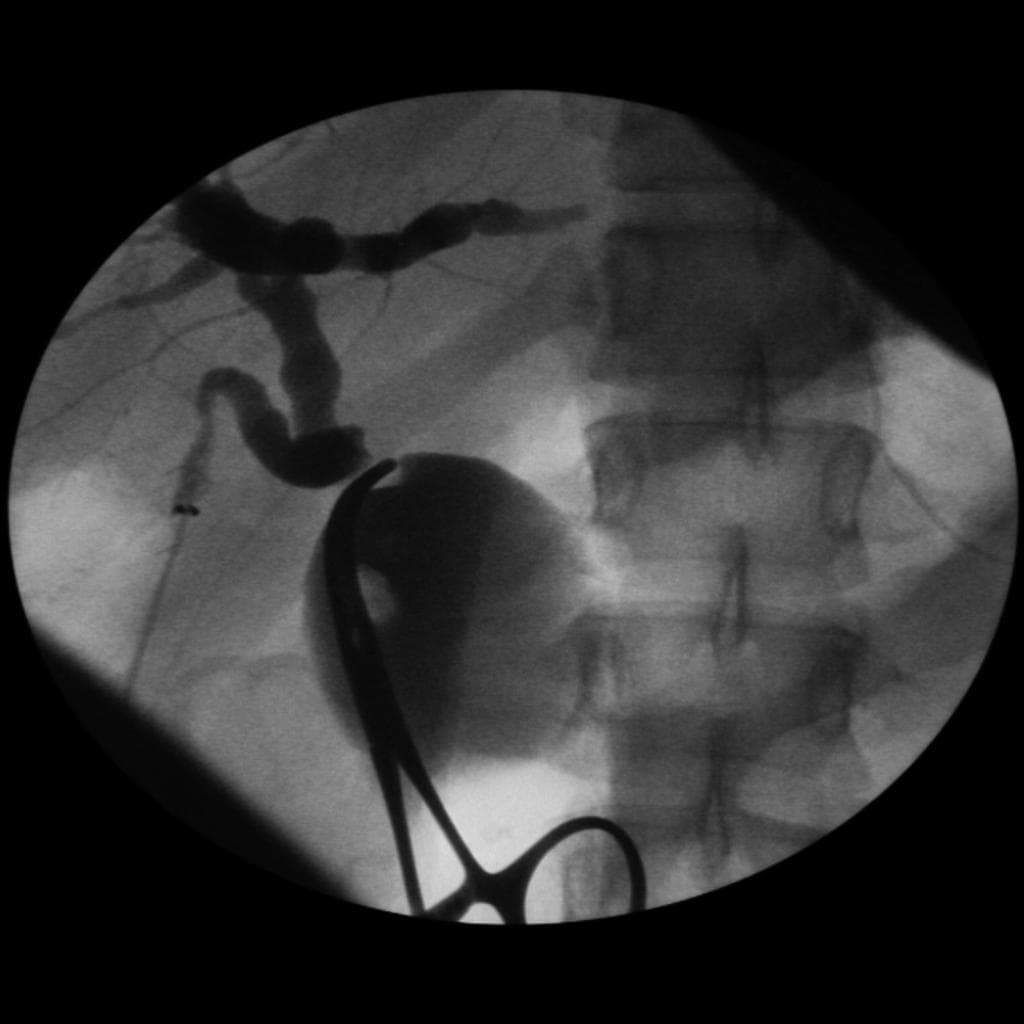

- Các tổn thương nang không thông với ống tụy chính (main pancreatic duct).

Chụp cộng hưởng từ (MRI) và cộng hưởng từ mật tụy (MRCP) tụy ở bệnh nhân mắc bệnh Von Hippel-Lindau cho thấy các nang tụy vô số (innumerable pancreatic cysts).

- "Tổn thương tụy trong VHL thường biểu hiện dưới dạng nhiều nang không thông với ống tụy chính hoặc u nang tuyến nước."